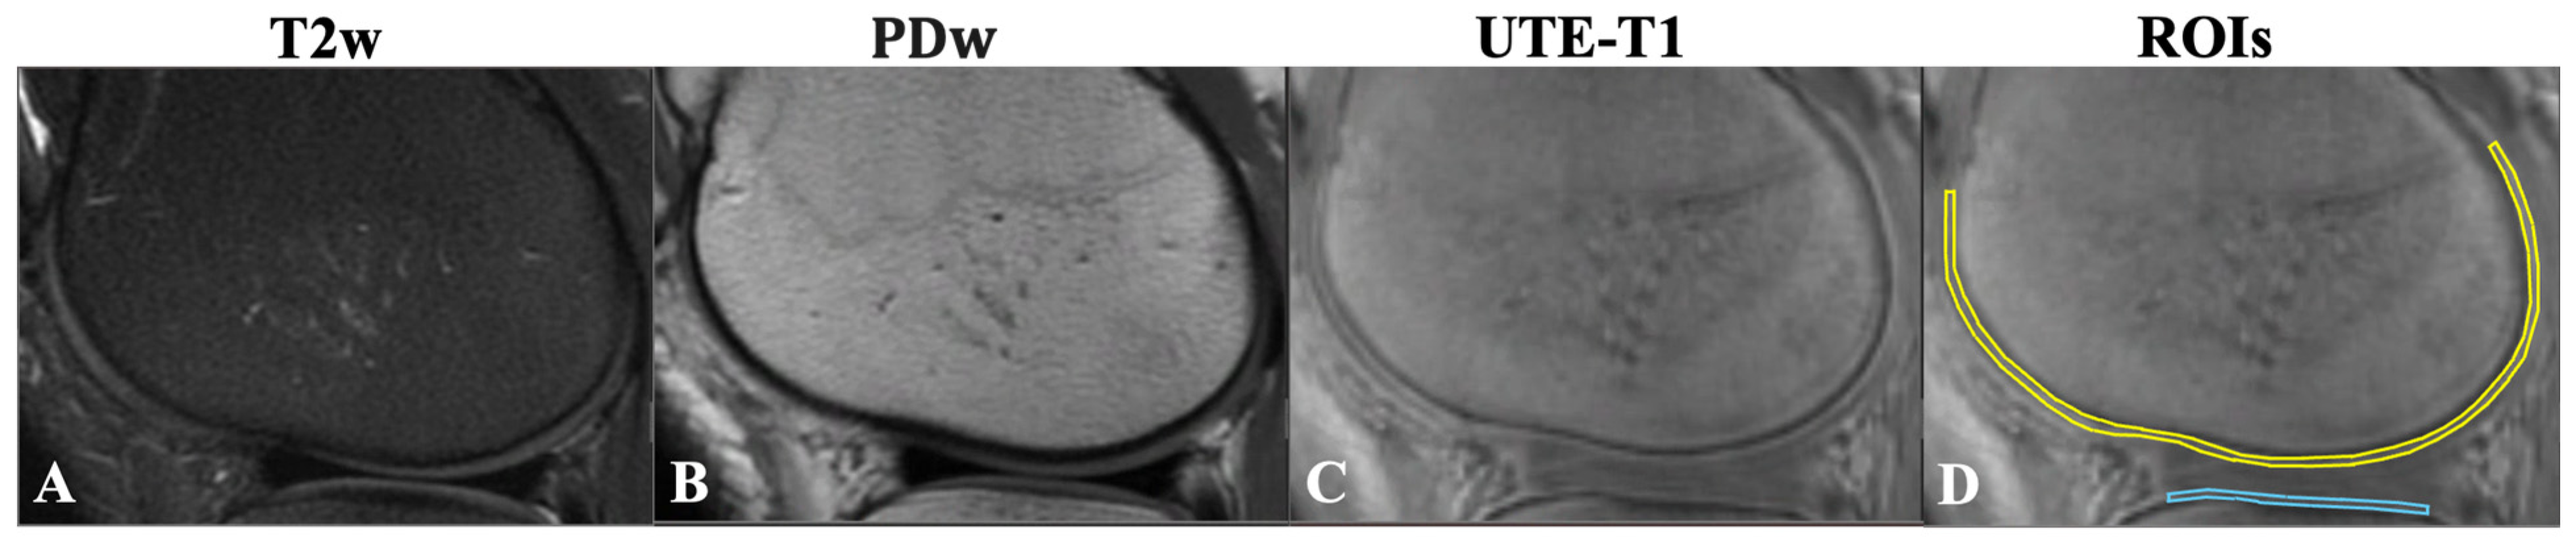

2.2. MRI Protocol

2.3. Data Analysis